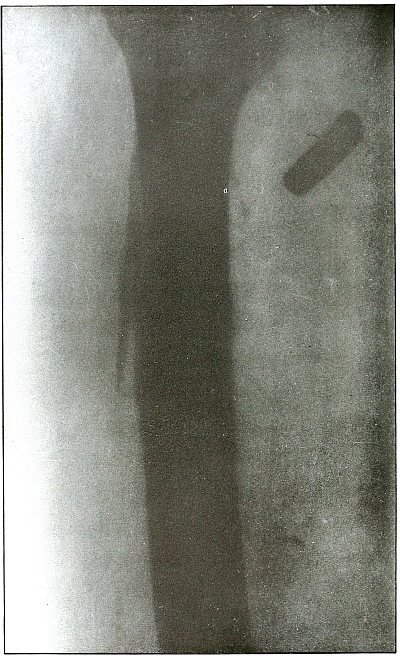

Plate 48.

[Pg 107]

Rifle—Plate 48.

LOWER EXTREMITY.

Gunshot Wound of the Thigh,

with Lodgment of the Bullet.

Wound of entrance, outer aspect of the thigh at the junction of the

upper and middle thirds.

The slight penetration without bone injury and with slight deformity

of the nose of the bullet indicates that the wound was caused by a

ricochet shot at extreme range, after its energy was almost spent.

With the posterior aspect of the thigh next to the plate, the dense

shadow and the nearly normal size of its outline indicate that the

bullet was in the same relative position and that it lay posterior to

the neck of the femur.

As such wounds are rarely infected, the treatment is conservative,

and a search for the missile is only justified by serious infection,

pain, or impaired function.